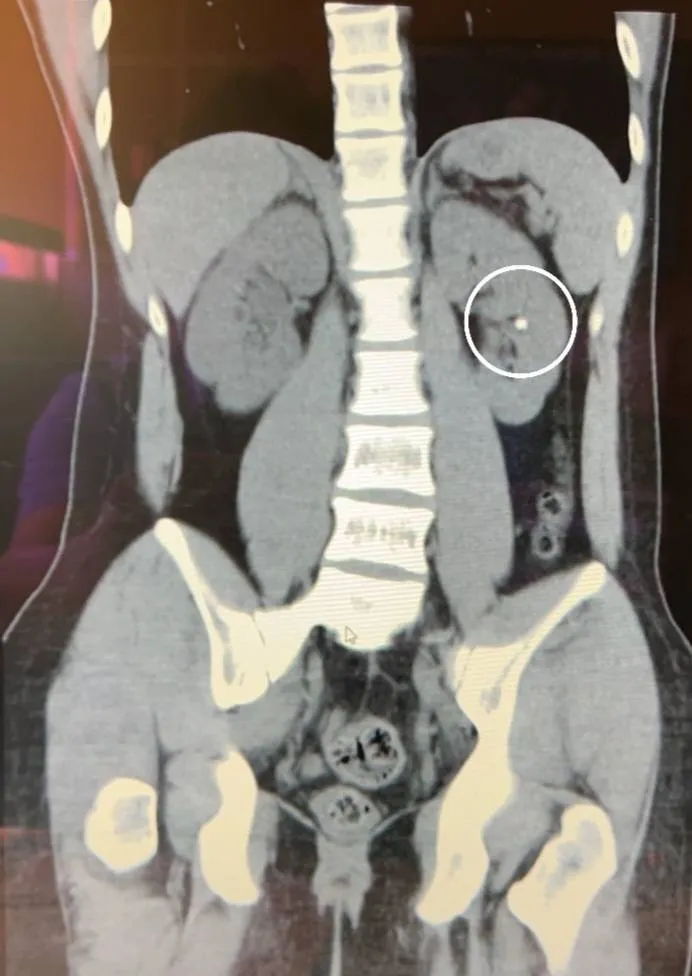

19歲「少年仔」因為少喝水、憋尿,年紀輕輕就結石,造成右腎積水,經常腰酸背痛。阮綜合醫院提供

蔡秉儒指出,通常腎結石不會造成泌尿道的阻塞、症狀不明顯,但是結石若不幸掉落到輸尿管造成阻塞,就會造成腰痛的情形,輸尿管結石阻塞有腰痛、血尿、發燒嘔吐等三大症狀,小顆的結石(小於0.5公分)在大量飲水、運動下有很高機率可排出體外,但排出速度及時間卻不可預期,從幾天到幾周都有。